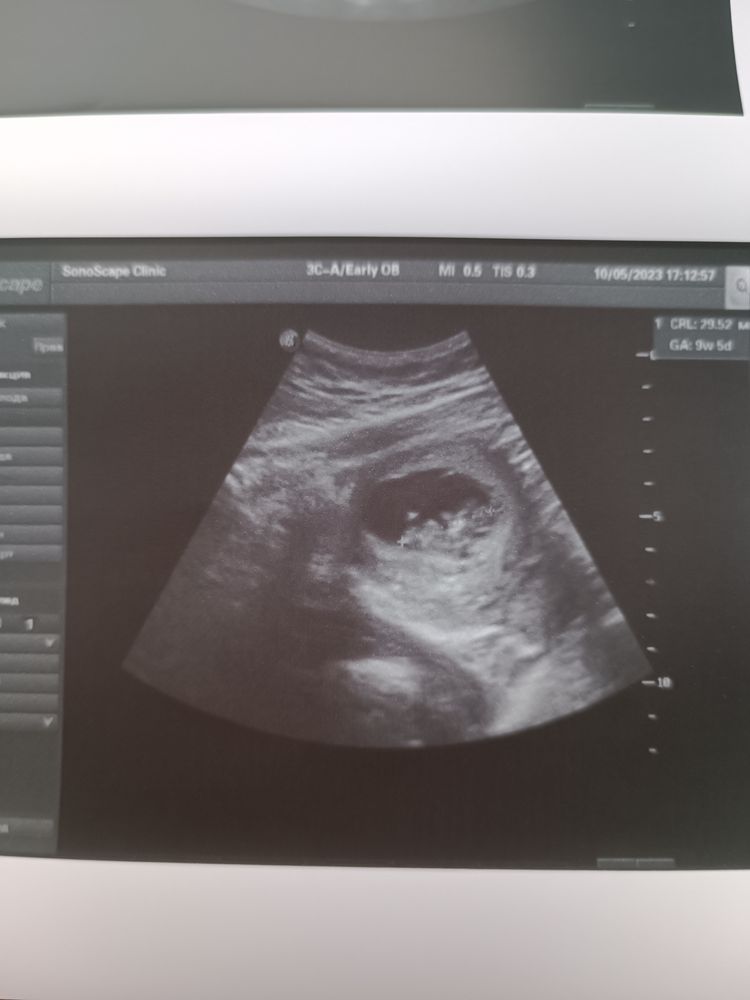

Всё хорошо, узи с моно моно 10 недель💞

Ирина Витальевна , у Вас получается, моно-моно? Перегородку не увидели?

Евгения , всё в порядке, но на перегородку еще надеюсь) Спасибо и вашим малышам тоже💖💗